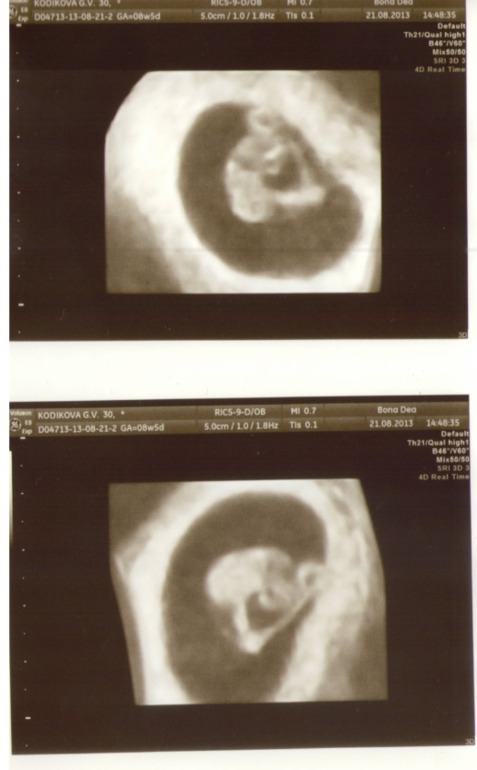

Сегодня мы были на УЗИ и наше сердечко бьется

Мы такие крохи

. По УЗИ нам 7 недель и 6 дней, а акушерские 8 недель и 5 дней, т.е. разница в 6 дней, норм. Догоняем (раньше была разница в почти 3 недели, т.к. О поздняя). ЧСС 170 ударов в минуту (тахикардия). Правда врач сказала, что это норм - не выходит за границы. И что это может быть из-за того что волнуется мамочка, ну и конечно же сам малышик. КТР 15мм. Желточный мешочек d=5мм. Желтое тело 19мм- в левом яичнике. И тут я была очень удивлена

! О у меня всегда была в ПЯ, а тут ЛЯ проснулся и какой то шустрик быстренько ее чик-чик

)))))